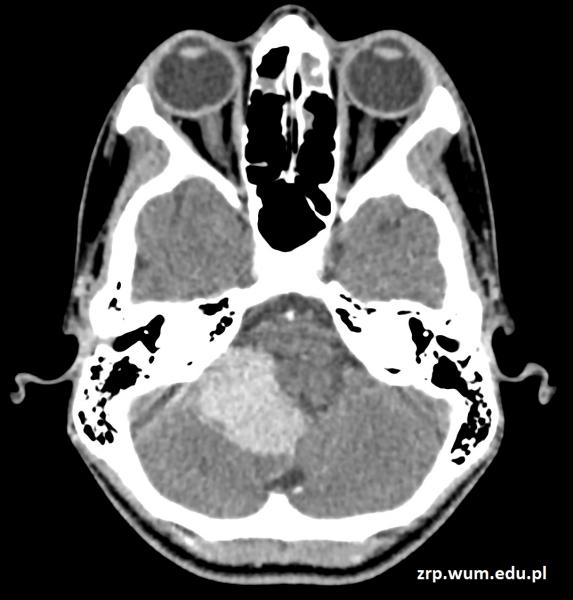

Przypadek 60: 3-latek po złamaniu przynasad dalszych obu kości przedramienia prawego. Badanie kontrolne po zdjęciu gipsu (4 tyg. po urazie).

Rozpoznanie: Na zdjęciach RTG widoczne nawarstwienia okostnowe / odczyny naprawcze w miejscu złamania prawej kości promieniowej, z jej niewielkim kątowym ustawieniem. Niewielkie nawarstwienia okostnowe w okolicy złamania prawej kości łokciowej.